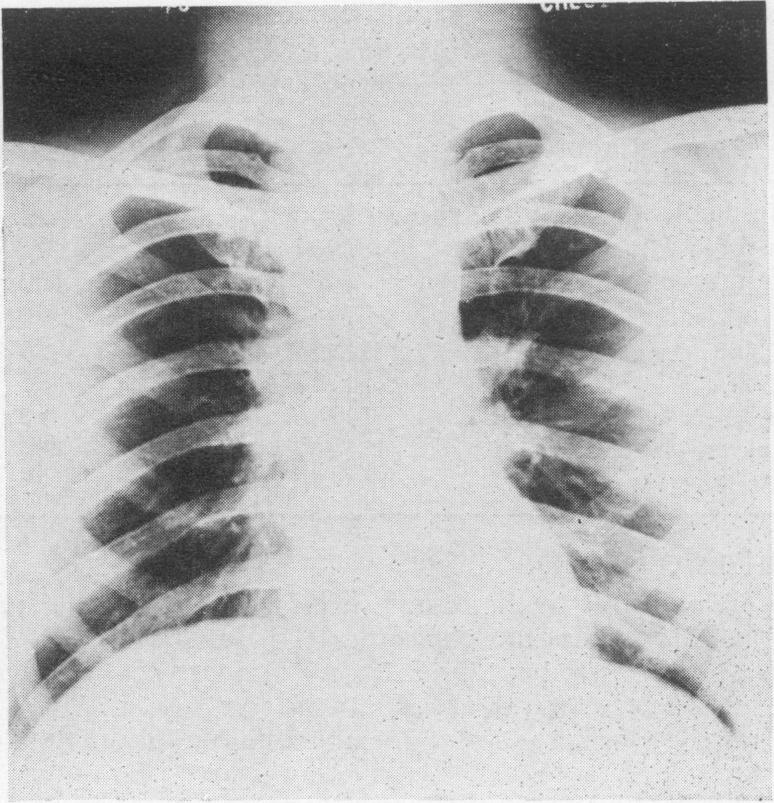

Mediastinoscopy: a diagnostic procedure in hilar and paratracheal lymphadenopathy.

Postgrad Med J. 1971 Nov;47(553):698-704. doi: 10.1136/pgmj.47.553.698.

Mediastinoscopy, in the skilled hands of a thoracic surgeon, is a safe, cosmetically accepted procedure with negligible complications, less than that reported in many series of scalene node biopsies. It has the advantage of yielding a much higher rate of diagnostic tissue, in all instances over 90%. In the cases of tuberculosis it enabled an organism to be isolated and sensitivities obtained. It has also revealed a group of cases with findings, a further study of which may increase our understanding, assessment and management of patients presenting with hilar and/or paratracheal lymphadenopathy.